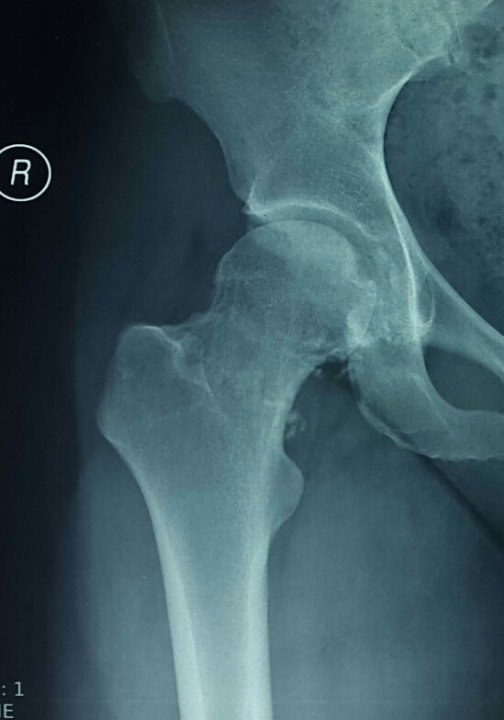

Η υμενική οστεοχονδρομάτωση του ισχίου είναι μία καλοήθης πάθηση με μονοαρθρική εντόπιση που όμως προκαλεί πλήρωση της άρθρωσης με πολλαπλά οστεοχόνδρινα σωμάτια. Αυτό μπορεί μακροπρόθεσμα να οδηγήσει στην εκφύλιση του ισχίου.

Η θεραπεία εκλογής είναι η αρθροσκοπική αφαίρεση των σωματίων και ο καθαρισμός της άρθρωσης. Σε αυτήν την ασθενή πραγματοποιήθηκε αρθροσκοπικός καθαρισμός και παρατηρήθηκε άμεση βελτίωση των συμπτωμάτων, κινητοποιήθηκε άμεσα και εξήλθε από την κλινική την ίδια μέρα.